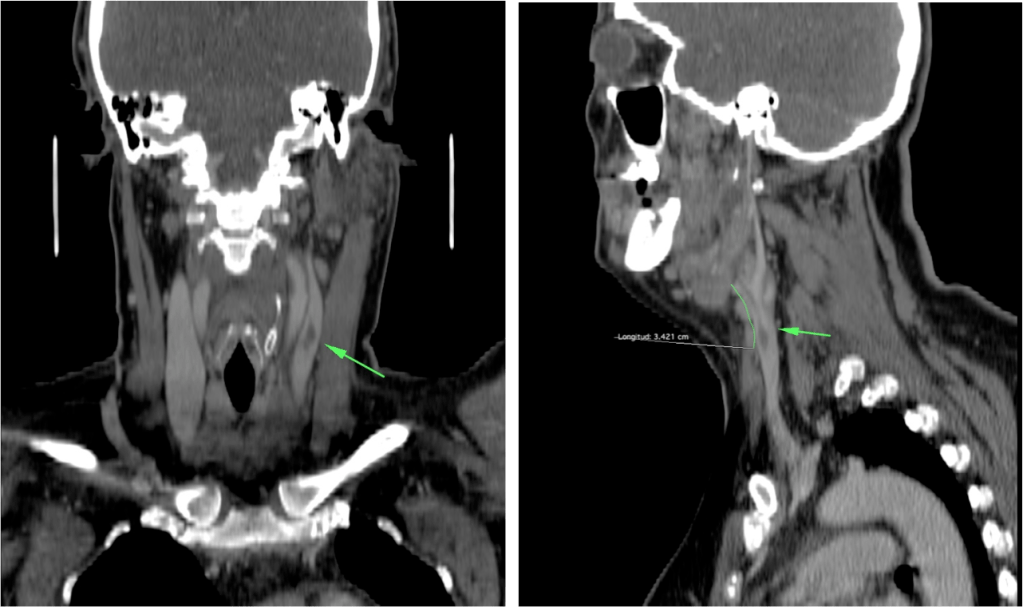

ESPACIO RETROFARÍNGEO:

En el adulto, este espacio contiene fundamentalmente grasa, mientras que los niños (hasta los 6 años) pueden presentar ganglios. Suele darse en niños e inmunocomprometidos por diseminación vía linfática de infecciones de tejidos adyacentes. La afectación de este espacio es muy importante porque puede extenderse al mediastino, normalmente entre los niveles D1 – D6

Hallazgos:

- Colección líquida con realce periférico en anillo, que ocupa y expande la retrofaringe, con o sin gas.

- Cuando se observa edema, fluidos o inflmación con aumento del espesor, hay que seguir caudalmente el espacio retrofaríngeo en indicar el punto donde vuelve a ser normal o hasta observar si existe o no afectación del mediastino.

- Determinar si existen complicaciones como: extensión al mediastino, compromiso de la vía aérea, asociación de espondilodiscitis o absceso epidural y compromiso del espacio carotídeo, que puede ocasionar trombosis de la vena yugular interna (Síndrome de Lemierre).